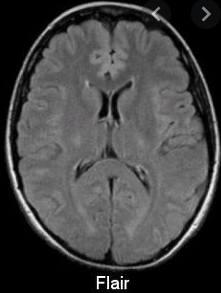

하지만 재정악화 및 무분별한 MRI 시행으로 또 제도가 바꼈습니다. 2020년 4월 1일에 개선안이 나왔는데요.

신경학적 검사상 이상 증상 또는 뇌혈관 질환이 강력하게 의심되는 경우에만 건강보험이 적용되는걸로 바꼈습니다.

그리고 뇌질환이 의심되는 두통, 어지로움으로 MRI 검사를 받았다면 본임부담이 80%로 바꼇습니다. 그렇기 때문에 의사의 판단하에 따라 금액이 많이 차이가 나게 되었습니다.